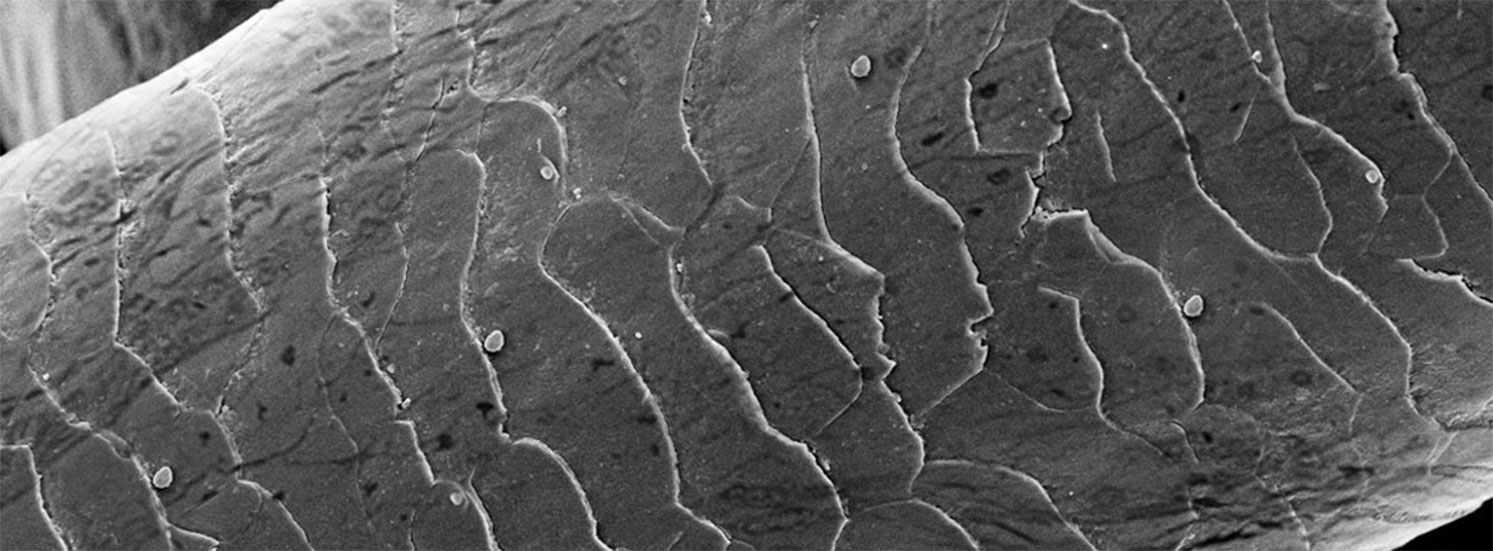

Les résultats de l’étude clinique de l’influence du peptide Epigenist sur l’épaisseur de l’épiderme

L’épaisseur de l’épiderme est indiquée par les flèches. 20 femmes qui demeurent à l’Union Européenne et qui se caractérisent par la peau sèche et la peau à problems (l’âge des femmes est égal à 45 à 55 ans) ont pris part à l’étude clinique

• D0 – le début de l’étude clinique.

• D28 – après 28 jours de l’usage.

• D56 – après 56 jours de l’usage.

*La microscopie à balayage laser (la microscopie confoncale) VivaScore® 3000.